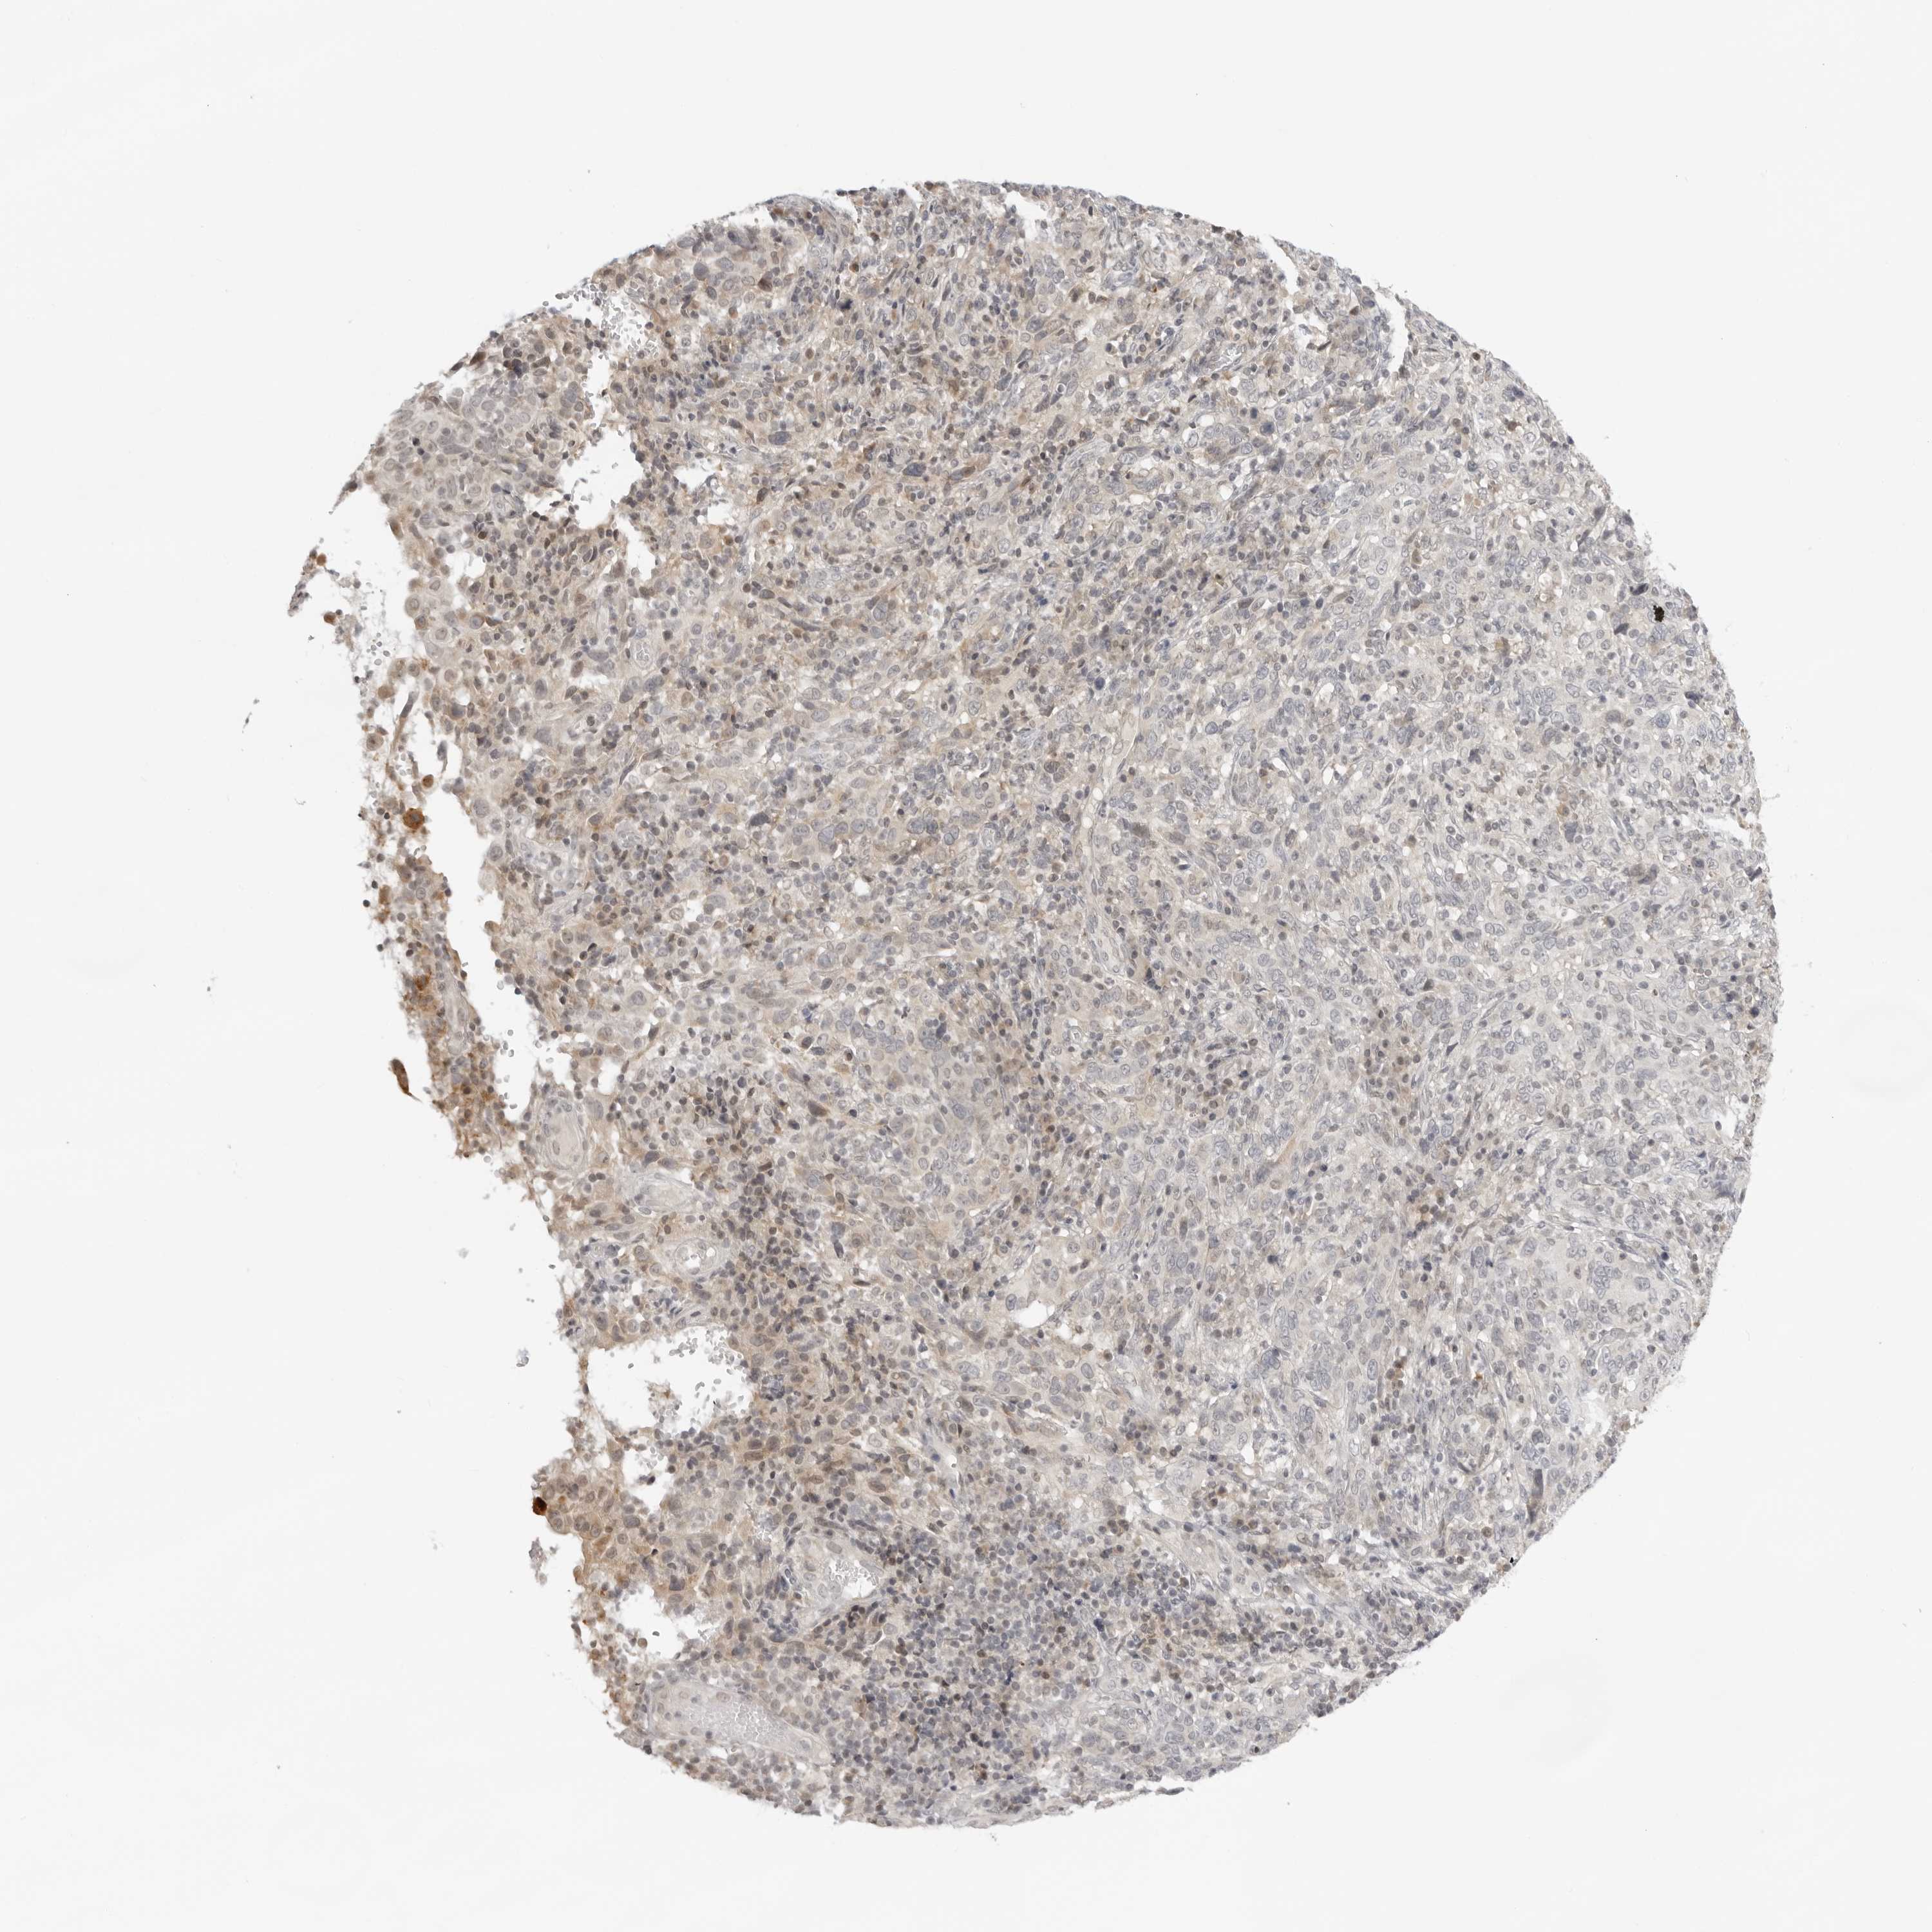

CERVICAL CANCER - Protein expressioni

A mouse-over function shows sample information and annotation data. Click on an image to view it in a full screen mode. Samples can be filtered based on level of antibody staining by selecting one or several of the following categories: high, medium, low and not detected. The assay and annotation is described here.

Note that samples used for immunohistochemistry by the Human Protein Atlas do not correspond to samples in the TCGA dataset.

Antibody stainingi

Antibody staining in the annotated cell types in the current human tissue is reported as not detected, low, medium, or high, based on conventional immunohistochemistry profiling in selected tissues. This score is based on the combination of the staining intensity and fraction of stained cells.

Each image is clickable and will lead to virtual microscopy that enables deeper exploration of all samples and also displays staining intensity scores, fraction scores and subcellular localization as well as patient and tissue information for each sample.

Antibody HPA028560

Staining

High

Medium

Low

Not detected

Intensity

Strong

Moderate

Weak

Negative

Quantity

>75%

75%-25%

<25%

None

Location

Nuclear

Cytoplasmic/membranous

Cytoplasmic/membranous,nuclear

Squamous cell carcinoma, NOS

Adenocarcinoma, NOS